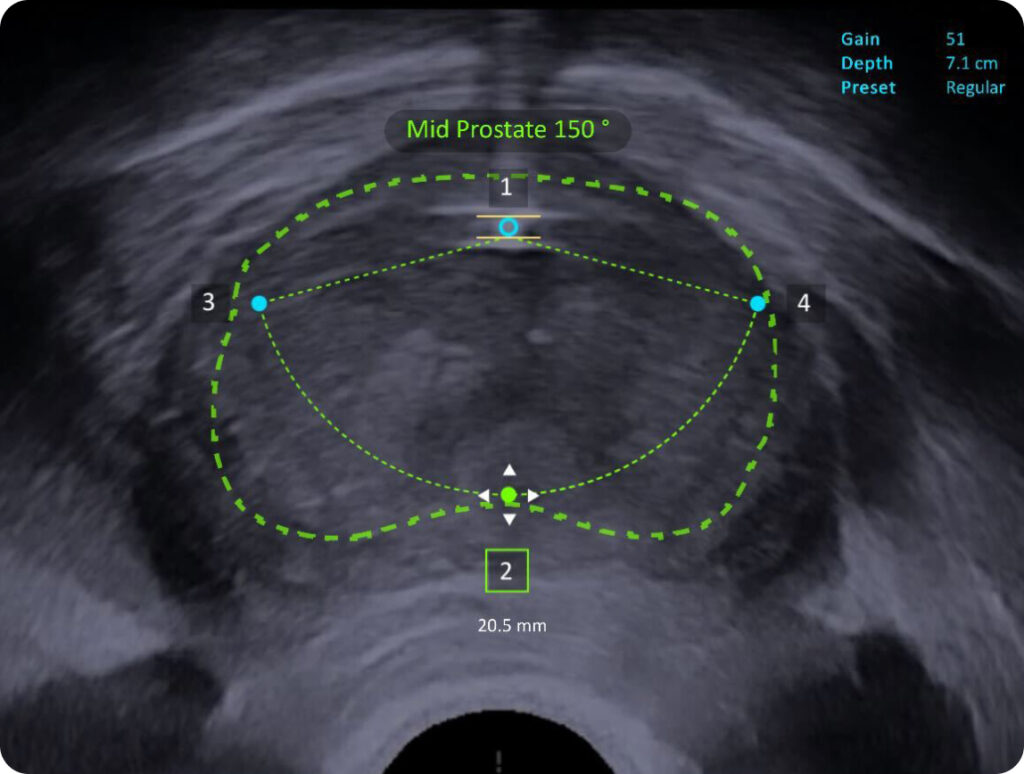

FirstAssist AI, built from a library of real-world Aquablation therapy procedures, uses advanced image recognition software to identify critical anatomy on ultrasound and suggest an optimal treatment plan for each patient.

Advanced Image Guidance

The system integrates next-generation ultrasound imaging, digital cystoscopy, and dual high-definition touchscreens providing enhanced visualization of the anatomy and simultaneous viewing of ultrasound and cystoscopy images. The integrated digital cystoscope offers higher resolution video and a wider field of view.